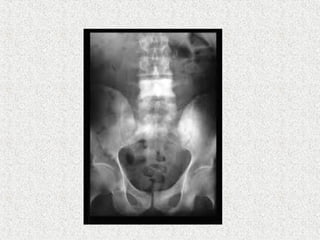

Can affect any bone

Commonly affects

Pelvis & tibia (commonest)

 Spine

 Picture frame sign

 Ivory vertebra

 Squaring on lateral view

 Vertical trabecular thickening

Can affect anybone Commonly affects Pelvis & tibia (commonest) Femur Spine 75%  Lumbar common  Cervical rare Cranium Monostotic or polyostotic Symtomatic or asymptomatic

 Spine  Pictureframe sign  Ivory vertebra  Squaring on lateral view  Vertical trabecular thickening